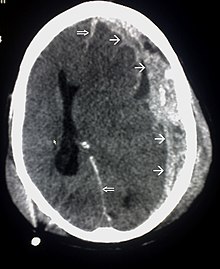

| CT scan showing cerebral contusions, hemorrhage within the hemispheres, and subdural hematoma. There is also displaced skull fracture of left transverse parietal and temporal bones.[2] | |

Hematomas, also focal lesions, are collections of blood in or around the brain that can result from hemorrhage.[24] Intracerebral hemorrhage, with bleeding in the brain tissue itself, is an intra-axial lesion. Extra-axial lesions include epidural hematoma, subdural hematoma, subarachnoid hemorrhage, and intraventricular hemorrhage.[105] Epidural hematoma involves bleeding into the area between the skull and the dura mater, the outermost of the three membranes surrounding the brain.[24] In subdural hematoma, bleeding occurs between the dura and the arachnoid mater.[32] Subarachnoid hemorrhage involves bleeding into the space between the arachnoid membrane and the pia mater.[32] Intraventricular hemorrhage occurs when there is bleeding in the ventricles.[105]

Surgery can be performed on mass lesions or to eliminate objects that have penetrated the brain. Mass lesions such as contusions or hematomas causing a significant mass effect (shift of intracranial structures) are considered emergencies and are removed surgically.[32] For intracranial hematomas, the collected blood may be removed using suction or forceps or it may be floated off with water.[32] Surgeons look for hemorrhaging blood vessels and seek to control bleeding.[32] In penetrating brain injury, damaged tissue is surgically debrided, and craniotomy may be needed.[32] Craniotomy, in which part of the skull is removed, may be needed to remove pieces of fractured skull or objects embedded in the brain.[138] Decompressive craniectomy (DC) is performed routinely in the very short period following TBI during operations to treat hematomas; part of the skull is removed temporarily (primary DC).[139] DC performed hours or days after TBI in order to control persistently high intracranial pressures (secondary DC), although can reduce intracranial pressure and length of stay in ICU, but have worse Glasgow Coma Scale (GCS) scores, and high chances of death, vegetative state, or severe disability when compared to those receiving standard medical therapies.[140][141][27][139]